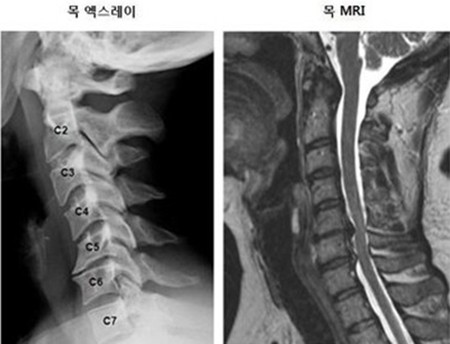

목 디스크 증상 총 정리 중 원인이고요. 한방 의학정보에 의하면 목 디스크는 목 뼈 사이 추간판이 파열됐거나 탈출되어 경추 신경의 자극, 압박으로 인하여 목, 어깨, 등, 팔 등 통증과 신경학적 증상이 있는 질환이예요.

경추는 제일 위쪽 목에 있는 7개의 뼈이라고 합니다. 경추는 운동성이 크므로 경추의 추간판은 압력에 의해 탈출되어 척수, 신경근을 억압되게 된다 하였습니다.